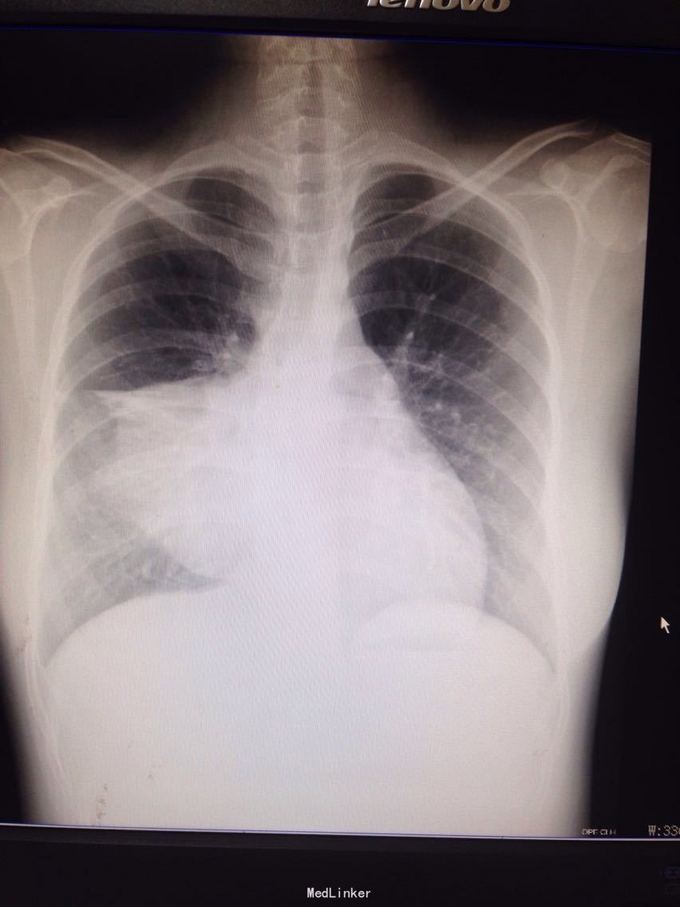

主诉:间歇性胸痛2年 病史:患者2年前无明显诱因出现胸痛,呈间歇性隐痛,约1至3月出现胸痛一次,每次持续约3-5天,近半年来感胸痛较前频发。并出现发作时胸闷、气促。至当地医院就诊,作胸部CT提示纵隔占位性病变。遂入我科手术治疗。

查体:双眼眼睑无明显下垂,结膜无充血,巩膜无黄染。双瞳孔等大等圆。气管居中,双侧胸廓无明显畸形,呼吸运动无受限。右侧中胸部叩诊浊音,左侧胸部叩诊清音,双肺呼吸音清,无啰音。 胸部CT提示右纵隔肿瘤。

诊断:右纵隔占位:畸胎瘤可能性大 处理:右侧前外侧切口第四肋进胸完成肿瘤切除,术中切开肿瘤见大量毛发形成,未见骨骼及牙齿形成